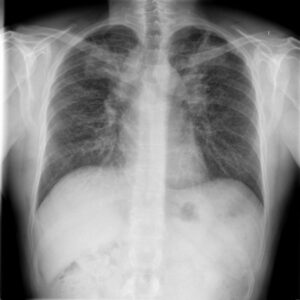

Two chest X-rays of a patient with silicosis taken one year apart, showing the progression of fibrosis.